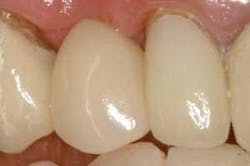

Figure 17 - Occlusal view of completed case. The occlusal view of the completed case shows broad, flat proximal contacts that facilitate proper esthetics and prevent proximal food and plaque entrapment.